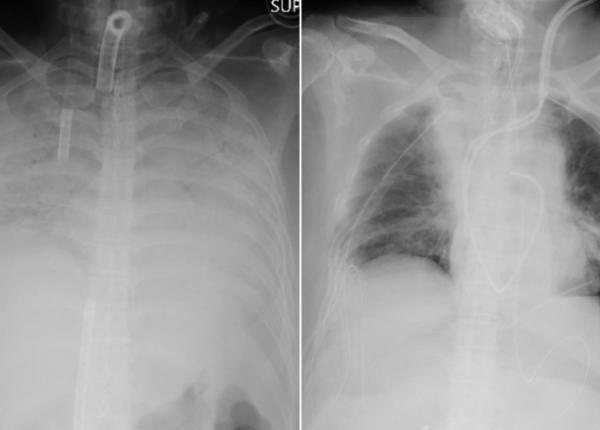

Simptomele COVID-19 s-au schimbat. Medic: aparent au evoluție bună, și la un moment familia primește un telefon că a decedat și nu înțelege ce se întâmplă

Boala COID-19 evoluează diferit, cu simptome mult mai grave, arată medicul Beatrice Mahler, managerul Institutului Marius Nasta.